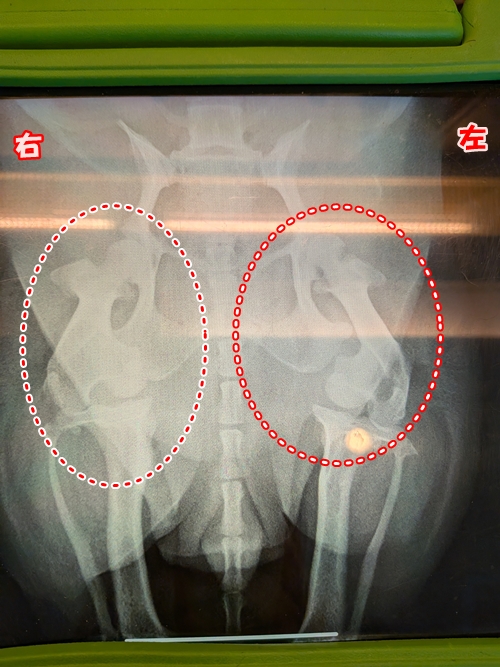

結果は・・・左後ろ足のひざが脱臼していました😰

骨には異常はなかったそうなのですが、関節の部分が左が明らかにズレているとのことで、関節炎かヘルニアの可能性も捨てきれないそうです😔

今回の診断は膝の脱臼ということだったのですが、因果関係のありそうな疑いのある関節炎、及びヘルニア(もしくは違う病気)を改善するための治療を今後も行う方針に決まりました。